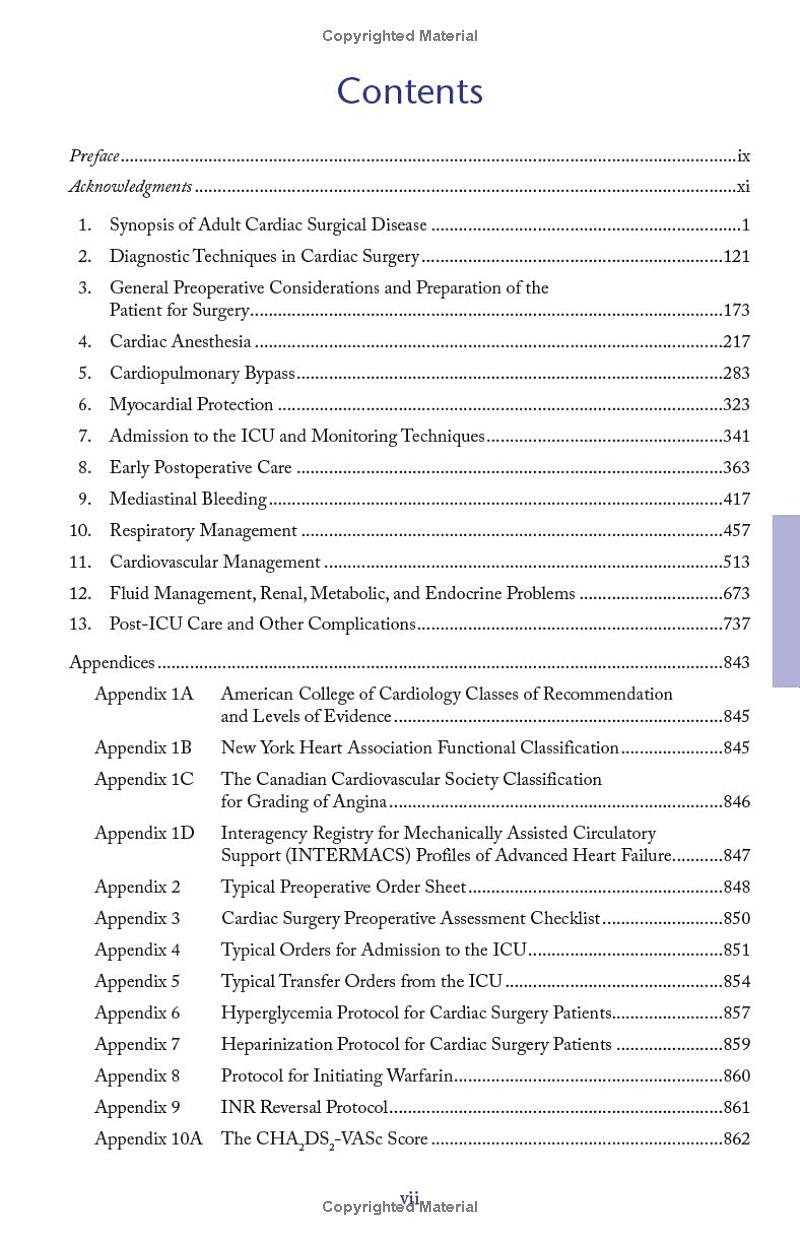

Now in its sixth edition, Robert M. Bojar’s Manual of Perioperative Care in Adult Cardiac Surgery remains the go-to practical guide for all of those involved in the care of the cardiac surgery patient. Written in outline format, it provides a comprehensive, detailed, and clearly explained review of cardiac surgical disease and perioperative management that is of value to practicing cardiac surgeons as well as to cardiologists, residents, fellows, advanced practice providers, critical care and floor nurses, perfusionists, and medical students.

Extensively rewritten with updated references to incorporate the latest concepts, guidelines, protocols, and medications used in cardiac surgical practice, this classic text retains the pragmatic features that have made it the gold standard reference that clinicians have used worldwide for the past 30 years.

Highlights include:

- Full coverage of cardiac surgical diseases, including pathophysiology, indications for surgery per guidelines, and figures of operative procedures and diagnostic techniques, with a panoply of examples

- Chronologic evaluation of patients from preoperative assessment to intraoperative considerations to postoperative care for each procedure

- Extensive chapters discussing organ system management in the ICU, followed by a discussion of later postoperative management and problems

- Incorporation of newer techniques (TAVR, Mitraclip, etc.) within the chronologic format

- Easy access to information using an outline format, markers on the free edges to identify chapters, synopsis pages at the beginning of each chapter, and a comprehensive index to provide easy referencing within the text

- Updated references throughout that are available from on-line resources

- 21 appendices summarizing order sheets, protocols, commonly used drug doses, body mass index, and other important information